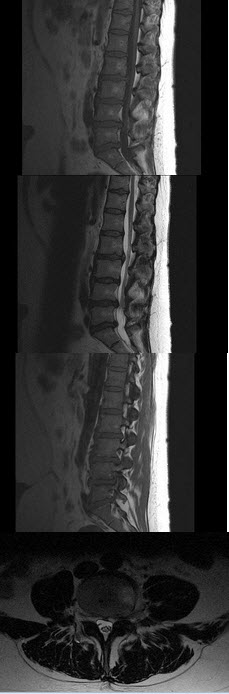

4、单项选择题  关于脊椎骨折,下列哪项不正确()

A.X线上椎体压缩变扁呈楔形改变

B.多发生在活动度较大的胸椎下段和腰椎上段

C.椎间隙变窄

D.严重时常并发脊椎后突成角,侧移

E.以单个椎体多见